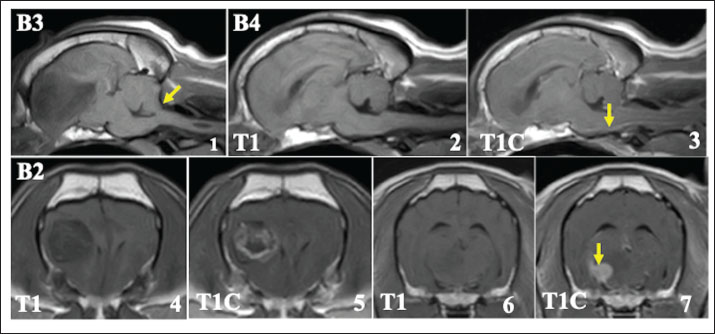

In this study, 4 cases could not complete the radiation therapy. Among these, 1 case died before starting treatment (B1), and 3 cases died during radiation therapy (B2–B4). Although the cause of death was not clearly identified because an autopsy could not be done, 2 cases that died after the first fraction showed cerebellar herniation on MRI at the first visit, possibly due to large tumor size (Fig. 5,1).

On MRI at the first admission in these 4 cases, leptomeningeal enhancement, as seen in cases A1–A4, was also observed, although the changes were less prominent (Fig. 5, 1-3). In 1 case (B2), multiple mass lesions were observed. In addition to the primary lesion, another presumed tumor tissue was observed, which appeared to be contiguous with the meninges on MRI, showing clear enhancement (Fig.5, 4-7).

Fig. 5. MRI at the first visit of the cases that died early after visiting our hospital (cases B2–B4, T1: T1-weighted image, T2: T2-weighted image, and T1C: T1-weighted image with contrast medium). Upper lane 1: Cerebellar herniation was observed on the sagittal plane (yellow arrow) in case B3, possibly due to the large tumor size. Upper lanes 2 and 3: At the time of the first visit, enhancement was already observed in the leptomeningeal region around the brainstem (B4, yellow arrow), but was less prominent compared with cases A1–A4. Lower lane 4–7: In case B2, the tumor tissue considered to be the primary lesion showed heterogeneous enhancement (4, 5). Furthermore, another mass contiguous with the meninges was observed. This mass shows a clear enhancement (6, 7, yellow arrow).